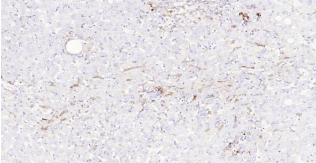

HLA-DR, like other MHC class II molecules, is a transmembrane glycoprotein composed of a 36 kDa alpha chain (DRA) and 27 kDa beta chain (DRB). The alpha chain gene contains 5 exons. Exon 1 encodes the leader peptide, exons 2 and 3 encode the two extracellular domains, and exon 4 encodes the transmembrane domain and the cytoplasmic tail. DRA does not have polymorphisms in the peptide binding part and acts as the sole alpha chain for DRB1, DRB3, DRB4 and DRB5. Within the DR molecule the beta chain contains all the polymorphisms specifying the peptide binding specificities. Hundreds of DRB1 alleles have been described and typing for these polymorphisms is routinely done for bone marrow and kidney transplantation. HLA-DR is expressed primarily on antigen presenting cells such as B lymphocytes, monocytes, macrophages, thymic epithelial cells and activated T lymphocytes. Three loci, DR, DQ and DP, encode the major expressed products of the human class II region. The human MHC class II molecules bind intracellularly processed peptides, present them to T-helper cells, and have a critical role in the initiation of the immune response.